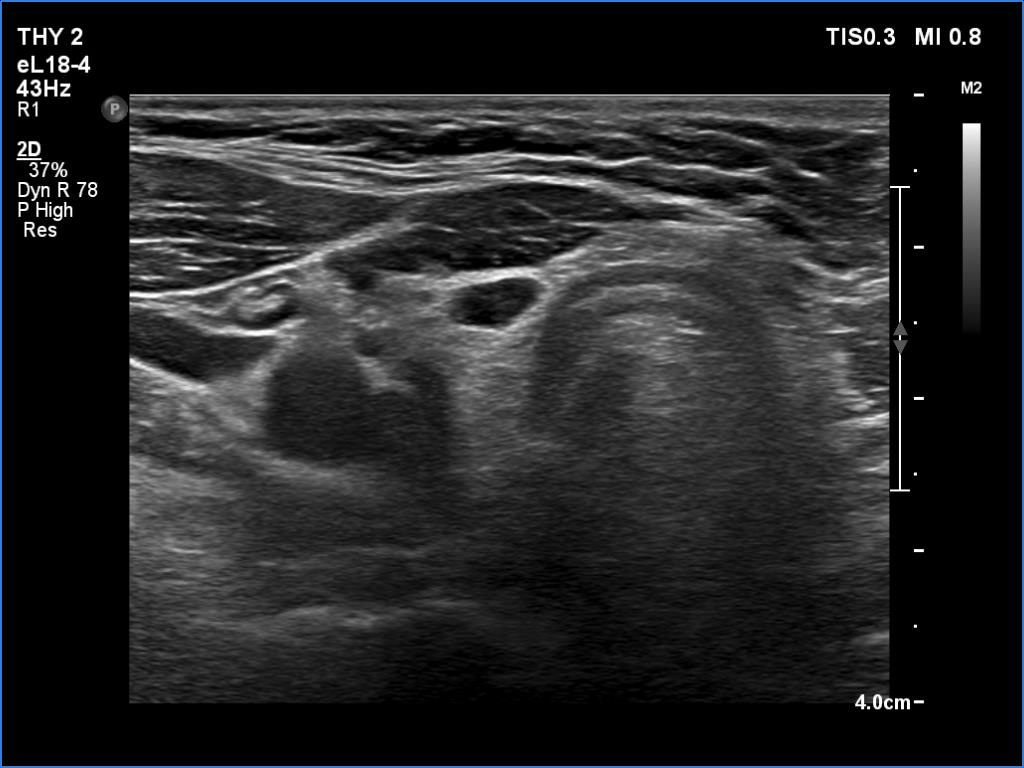

Lymphocytic thyroiditis - case 897

Examination one

Six month later

Focal form of lymphocytic thyroiditis is presented. At the first examination, beside smaller hypoechoic areas, the left lobe had a larger discrete lesion. It was doubtful whether this should be regarded as pathological nodule or not. In the first case, the lesion is an EU-TIRADS 5 nodule due to the irregular margins while in the latter, this is an EU-TIRADS 1 lesion. Six months later, the lesion had virtually disappeared which means that this was not a true nodule.